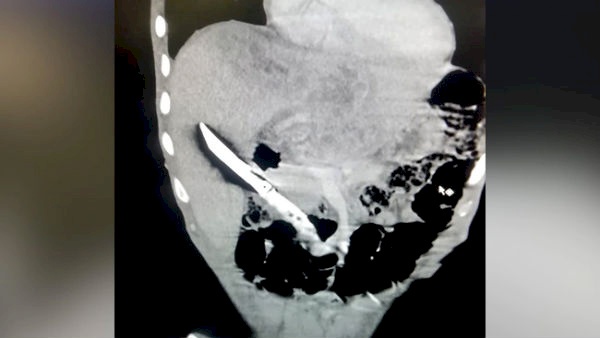

صورة: حدث في الهند.. ابتلع سكيناً طوله 20 سم ولم يمت!

صدى نيوز: أفادت وسائل إعلام هندية بأن شابا نجا بأعجوبة بعد عملية جراحية استمرت لنحو 3 ساعات، لإخراج سكين بطول 20 سم.

في التفاصيل، نقلت الصحف والمواقع الإلكترونية في الهند بأن الكوادر الطبية في أحد مستشفيات مدينة بالوال بولاية هاريانا الهندية أصيبت بالذهول بعد إزالة سكين بطول 20 سم من كبد شاب.

وكشفت الموجات فوق الصوتية والأشعة السينية للبطن شفرة سكين مطبخ عالقة في الكبد، كما أنها تسببت في نتوءات وتعفن في الدم.